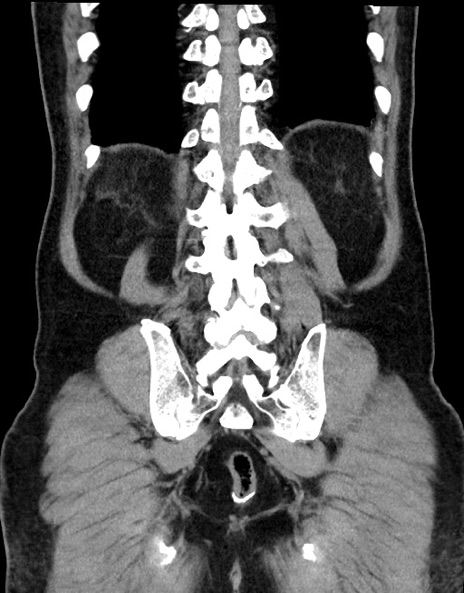

症例15(冠状断像)

【症例】70歳代男性

【主訴】腹痛

【現病歴】今朝から腹痛あり。全体的に痛い。特に左上の方。排ガスが今日はない。冷や汗が出る。

【既往歴】直腸癌術後

【身体所見】左側腹部〜上腹部に圧痛あり。腹膜刺激症状明らかなではない。軽度反跳痛。左下腹部に術後瘢痕あり。

【データ】WBC 7700、CRP 0.02